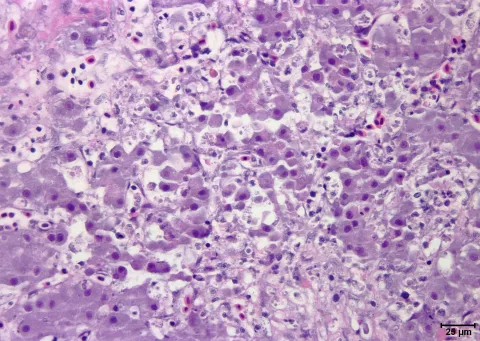

Liver damage caused by Piscirickettsia salmonis.

liver

H&E

Light Micrograph